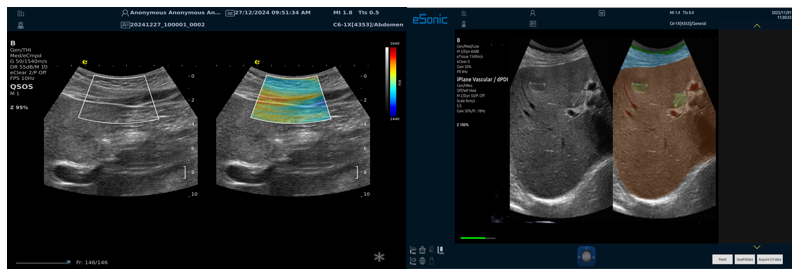

RTSWE实时剪切波弹性成像

?探头发射激励脉冲进行多点动态聚焦,利用马赫圆锥原理,形成大量的剪切波信号?颜色的变化与剪切波的速度相关,可直接体现肌肉肌腱等组织硬度值?实时、全幅、全定量

肌骨png.png

鉴别诊断、精准分级、定量评价、穿刺引导、疗效评估、随访观察

8a026746049f826559ab090aadef77f.png

9343ee4c6421309eedd3d2c0d2a5f32.png